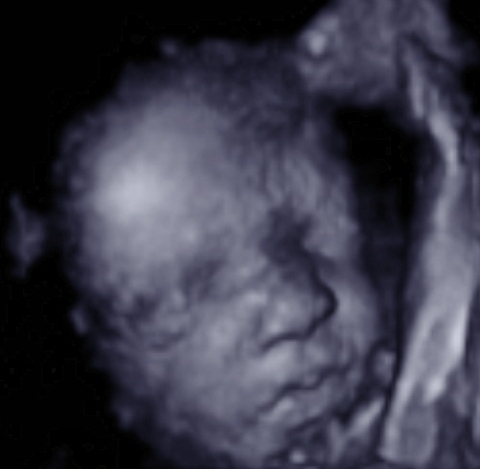

Here’s how ultrasound works in pregnancy: As early as 16 weeks, women can see a “fetal portrait” of their baby and determine its gender. Ultrasound technology has improved dramatically over the decades from flat, grainy black and white images to the current three-dimensional time experience.

Most hospitals offer some 3D scanning, but 3D ultrasound produces images that show the width, height and depth of a developing child. Rather than sending sound waves straight into the womb and recording when they bounce back as is common in 2D imaging, 3D ultrasound sends sound waves from different angles. A computer then renders a 3D image based on this data.

4D ultrasound adds movement as it occurs. The fourth dimension is time. You’re actually watching your baby live in 3D mode. How cool is that?